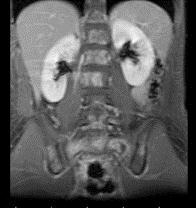

问题 7岁,男,发热、消瘦,数月前触及颈部淋巴结肿大,CT和MR检查如图,请选择最可能的诊断 ( )

选项 A、转移性淋巴肿大 B、胸腺瘤 C、结节病 D、淋巴结核 E、淋巴瘤

答案 E